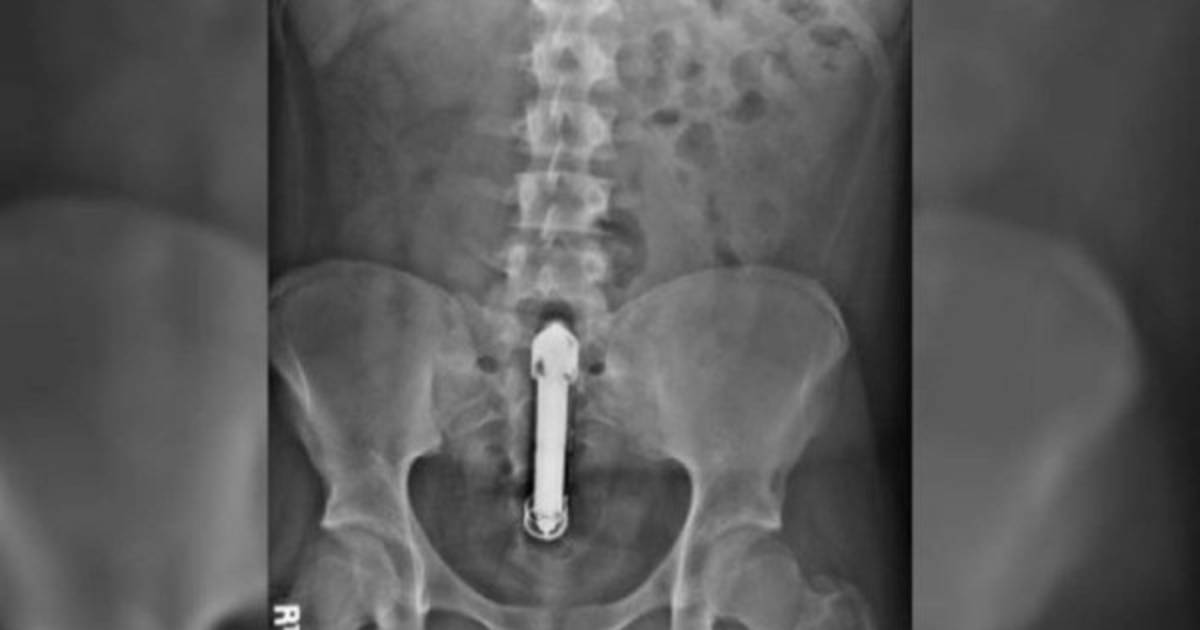

Los médicos revelaron que el vibrador había perforado su intestino.

Los médicos revelaron que el vibrador había perforado su intestino, lo que lo llevó a un fallo multiorgánico, sepsis y una perforación en el intestino.